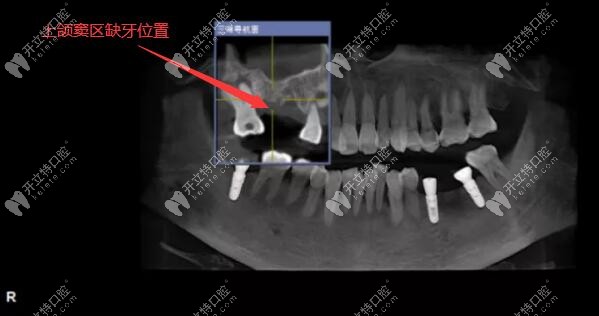

上頜后牙區(qū)骨量重度不足,做上頜竇外提升+同時植入種植體

牙槽骨量不足也能做種植牙哦~~~不信,來看51歲阿姨下頜后牙區(qū)骨量重度缺失,做上頜竇外提升的同時植入韓國奧齒泰種植體,是在深圳同步齒科做的哦!

用3D數(shù)字化導(dǎo)板技術(shù)做上頜竇區(qū)的精準(zhǔn)種植牙案例

今日分享:用3D數(shù)字化導(dǎo)板技術(shù)做上頜竇區(qū)的精準(zhǔn)種植牙案例,植入的是美國皓圣3508和4507型號的種植體。